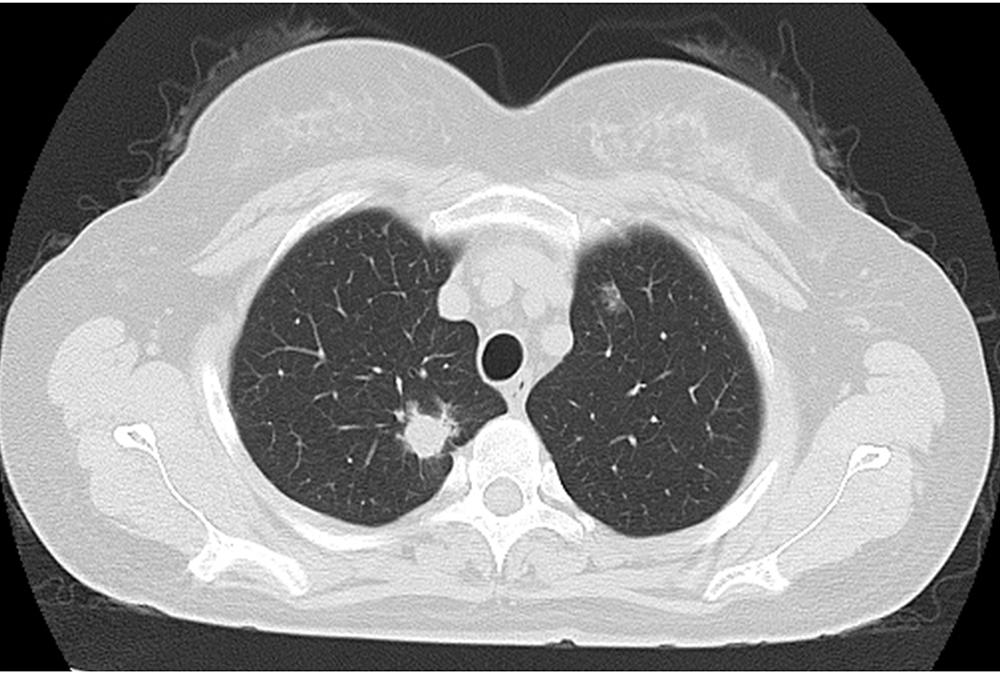

摘要:

ObjectiveTo investigate the correlations between multi-slice spiral CT (MSCT) atypical pleomorphic signs and pathological findings of lung metastases.MethodsFrom January 2012 to July 2019, the MSCT chest imaging data of 168 metastatic tumor of lung from the General Hospital of Central Theater Command of the Chinese People's Liberation Army and Shaanxi Provincial Tumor Hospital were collected. According to the pathological type, they were divided into metastatic adenocarcinoma group (n=88) and metastatic squamous cell carcinoma group (n=80). The atypical imaging signs of MSCT of the two groups were observed and recorded, and classified after labeling one by one. The difference of atypical MSCT imaging features between the two groups was compared, and the correlations between lesion size and atypical imaging features of MSCT in the metastatic adenocarcinoma group and metastatic squamous cell carcinoma group were analyzed.ResultsThe spicule sign in metastatic adenocarcinoma and metastatic squamous cell carcinoma were 61 (69.32%) and 28 (35.00%), with a statistically significant difference (χ2=19.811,P<0.001). The pleural depression sign in the two groups were 48 (54.55%) and 16 (20.00%), and there was a statistically significant difference (χ2=21.206,P<0.001). The vacuole/cavity sign in the two groups were 10 (11.36%) and 61 (76.25%), and there was a statistically significant difference (χ2=72.303,P<0.001). The air bronchial sign in the two groups were 43 (48.86%) and 13 (16.25%), with a statistically significant difference (χ2=20.057, P<0.001). The halo sign/ground glass shadow in the two groups were 58 (65.91%) and 37 (46.25%), with a statistically significant difference (χ2=6.591,P=0.010). The results of the Spearman rank correlation analysis indicated a positive correlation between the size of metastatic adenocarcinoma and spicule sign, pleural depression sign (r=0.270,P=0.011;r=0.226,P=0.035). There was no correlation between the nodule size and atypical MSCT imaging features in metastatic squamous cell carcinoma (allP>0.05).ConclusionThe atypical MSCT of metastatic lung adenocarcinoma are mostly spicule sign, pleural depression sign, air bronchial sign and halo sign/ground glass shadow. The characteristic atypical imaging of metastatic squamous cell carcinoma is vacuole/cavity sign. The spicule sign and pleural depression sign are related to the size of metastatic lung adenocarcinoma nodules.